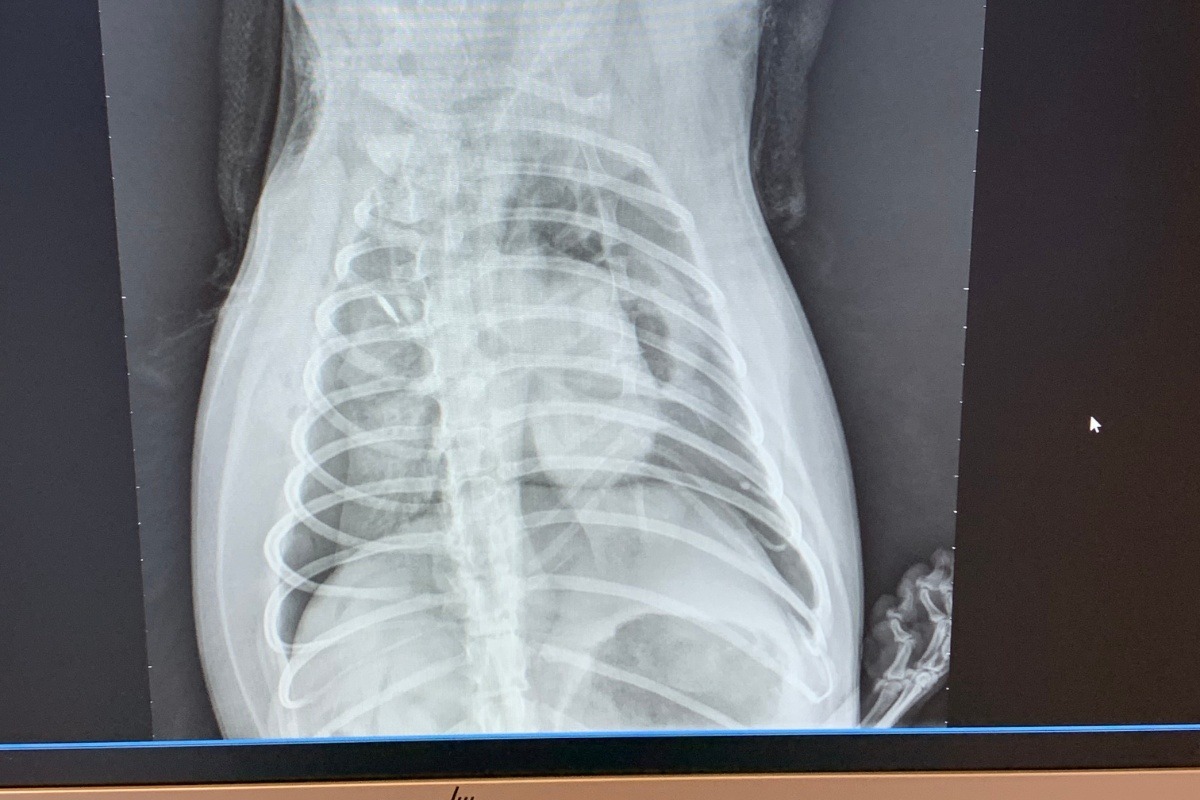

I took my dog, Spock out on a walk at the park yesterday (3/23/2020) and she was attacked by a Pit Bull. The Pit Bull got a hold of her right, front leg and Spock had it torn away from her, including her shoulder blade. She no longer has a (right) front leg, her right lung collapsed due to shock, and she sustained trauma to her chest cavity. As of right now, i'm unsure if she will survive this but the vet told me they would do anything they can to save her.I had Spock since I was 13 years old when she was just a small puppy and she has been with me while growing up. This tragedy is absolutely heartbreaking. I just cannot imagine the pain she is going through.